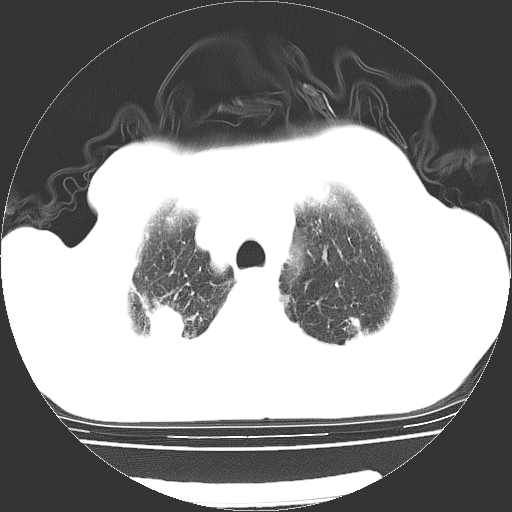

男,72岁,反复咳嗽、憋气一年余,有15年的煤矿井下工作史。

两上肺为主的大小不等结节影伴广泛纤维化,结合病史考虑尘肺。

1、双肺中上叶结节影结合病史考虑巨块型矽肺结节。

2、慢支炎并肺气肿

3、双下肺纤维化灶并左下肺局限性肺气肿。

支持 尘肺,肺心病?-------15年的煤矿井下工作史,双上肺叫对称的片团结节影,内见斑状钙化,边缘见粗长毛刺影,肺纹理混乱,可见网状及磨玻璃样影,肺门纵膈见多个淋巴结钙化